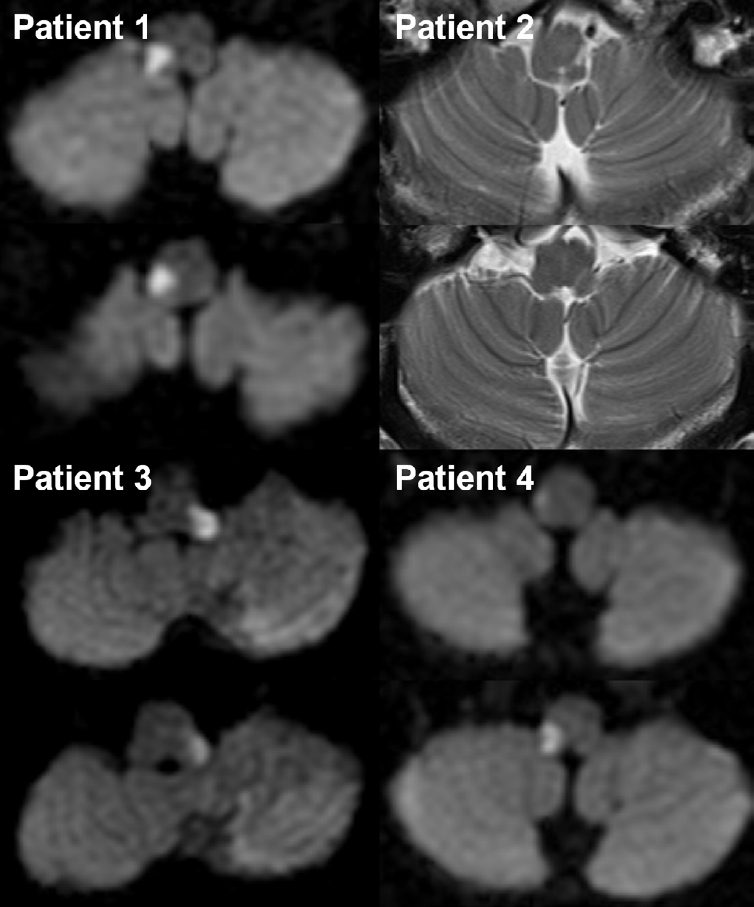

Trigeminal Autonomic Cephalalgias Following Unilateral Dorsolateral Medullary Infarction: A Case Series and Literature Review

Jae-Myung Kim, Hak-Loh Lee, You-Ri Kang, Joon-Tae Kim, Seung-Han Lee

Headache Pain Res. 2025;26(3):218-225.

Original ArticleOctober 22, 2025